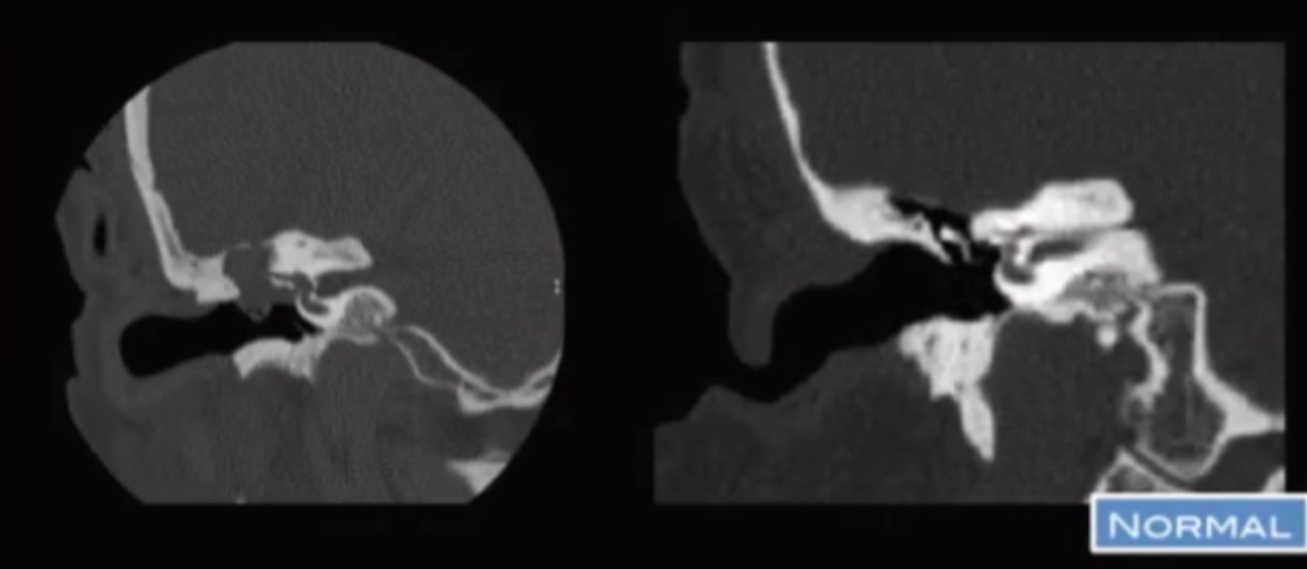

Absent Vertical Carotid Canal

• So basically carotid artery has to come straight up from neck to the brain obviously

• If your are missing the vertical portion in the carotid canal it will look like this where you have this soft tissue density looking thing horizontally oriented

• Also notice vs the normal the lack of the vertically oriented part of the carotid canal

• Do not biopsy - common question

• Happens because there is regression of the cervical carotid artery and will have enlargement of the collaterals that are through the middle ear